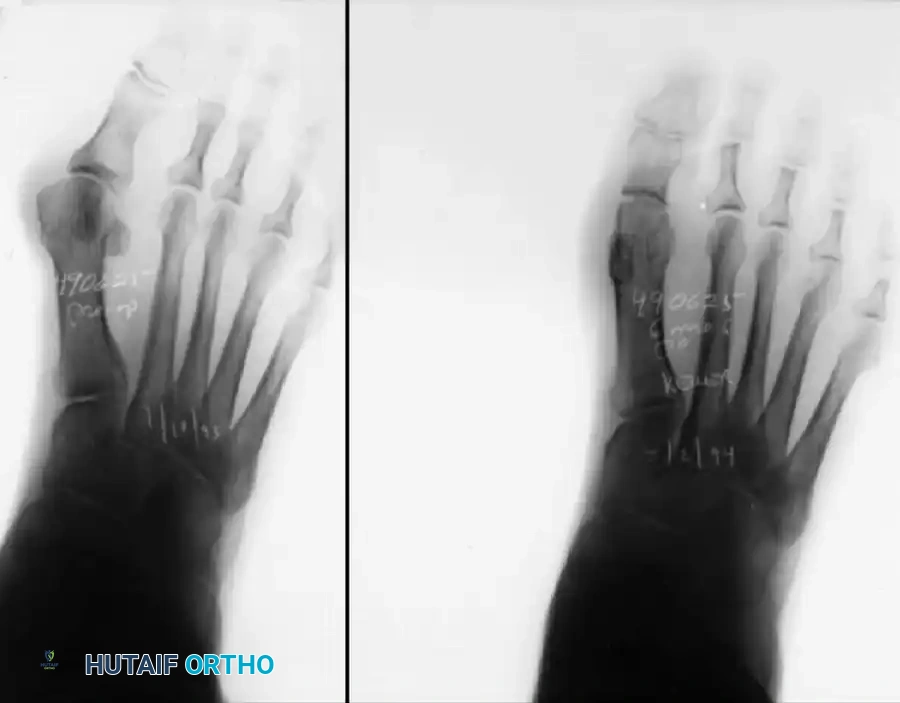

Patients presenting with 50 degrees or more of hallux valgus, 18 to 20 degrees of first metatarsal varus, complete lateral dislocation of the sesamoids, marked degenerative changes, and severe pronation of the hallux can achieve excellent functional and cosmetic outcomes when these modifications are integrated into the standard technique.

Figure 3: Severe hallux valgus with prominent bursa formation in a 70-year-old woman. Anteroposterior and lateral clinical photographs demonstrate the profound nature of the deformity.

Figure 4: Postoperative clinical photograph and weight-bearing radiographs of the same patient demonstrating excellent correction of the deformity utilizing the modified Keller procedure.